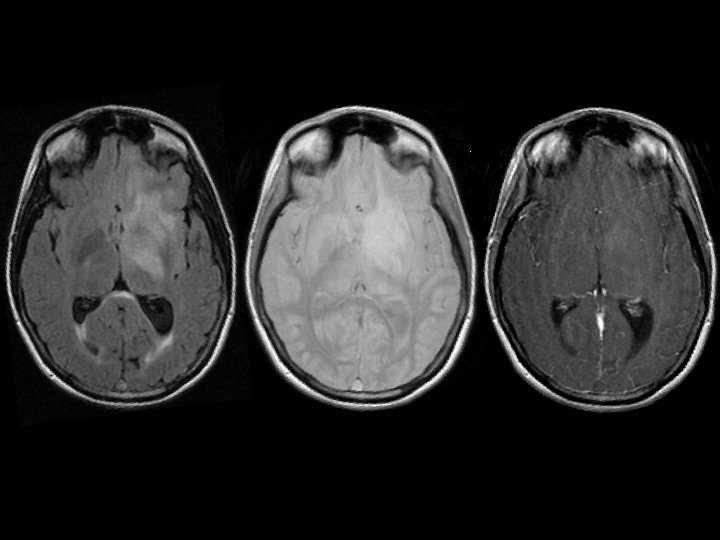

Primary Intracerebral Lymphoma • Findings: – T 2 bright lesion in the left frontal lobe and basal ganglia – Crosses both gray and white matter – Some mass effect – No significant enhancement • An unusual lesion in the non. HIV/immunosuppred population • ddx: – Low –grade glioma